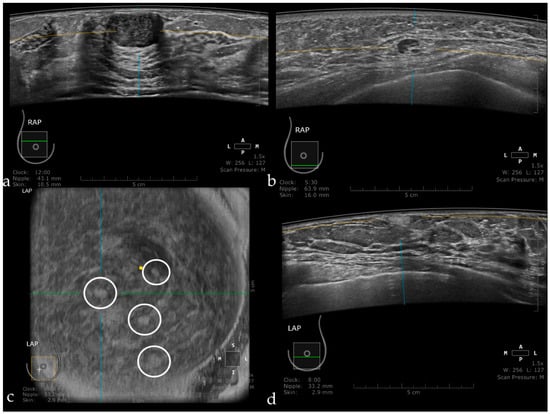

Figure 10 illustrates benign lesions detected using ABUS.

Figure 10. Fibroadenoma appearing as a hypoechoic, circumscribed mass, with the long axis parallel to the skin (a). Intramammary lymph node seen as a circumscribed mass, with a hyperechoic center representing the hilum and a thin cortex in the periphery (b). Multiple angiolipomas observed on the coronal plane (inside the white circles) (c), and also on axial acquisition as a hyperechoic, homogeneous, circumscribed mass (d).